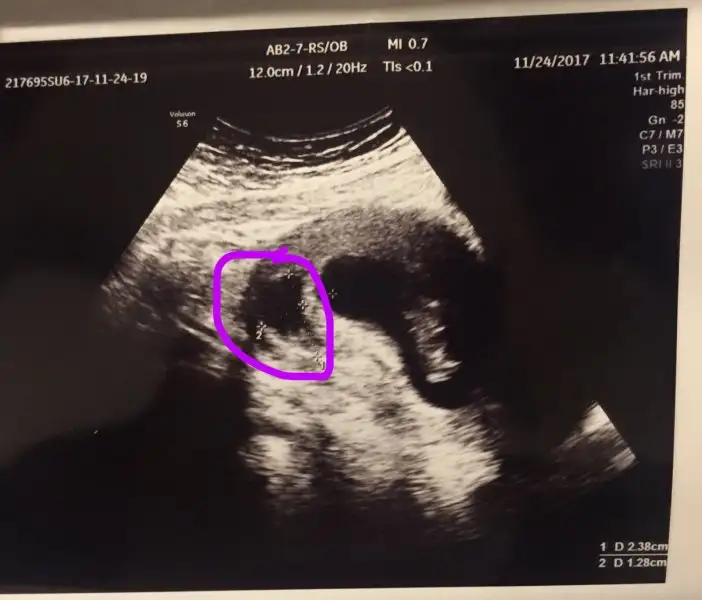

ekte de görüntüsünü paylaştım kanama alanı dediği yerin, siz de böyle bi şey olur da doktorun gözünden kaçan vs olursa diye görün istedim,

Selam kızlar ben de dün 11. haftama giriş günümde kontrole gittim, doktorum kesenin arkasında kanama alanı oluşmuş hemen progestana başlayalım dedi 200 ml olandan verdi ve günde 2 kere fitil olarak al, düşük tehlikesi yaratabilir dedi moralim bozuldu baya.

bende de şimdiye kadar kanamayı geçtim ufak bi lekelenme bile olmamıştı kanama alanı da baya büyük dedi doktor, o kadar üzüldüm ve tedirgin oldum ki